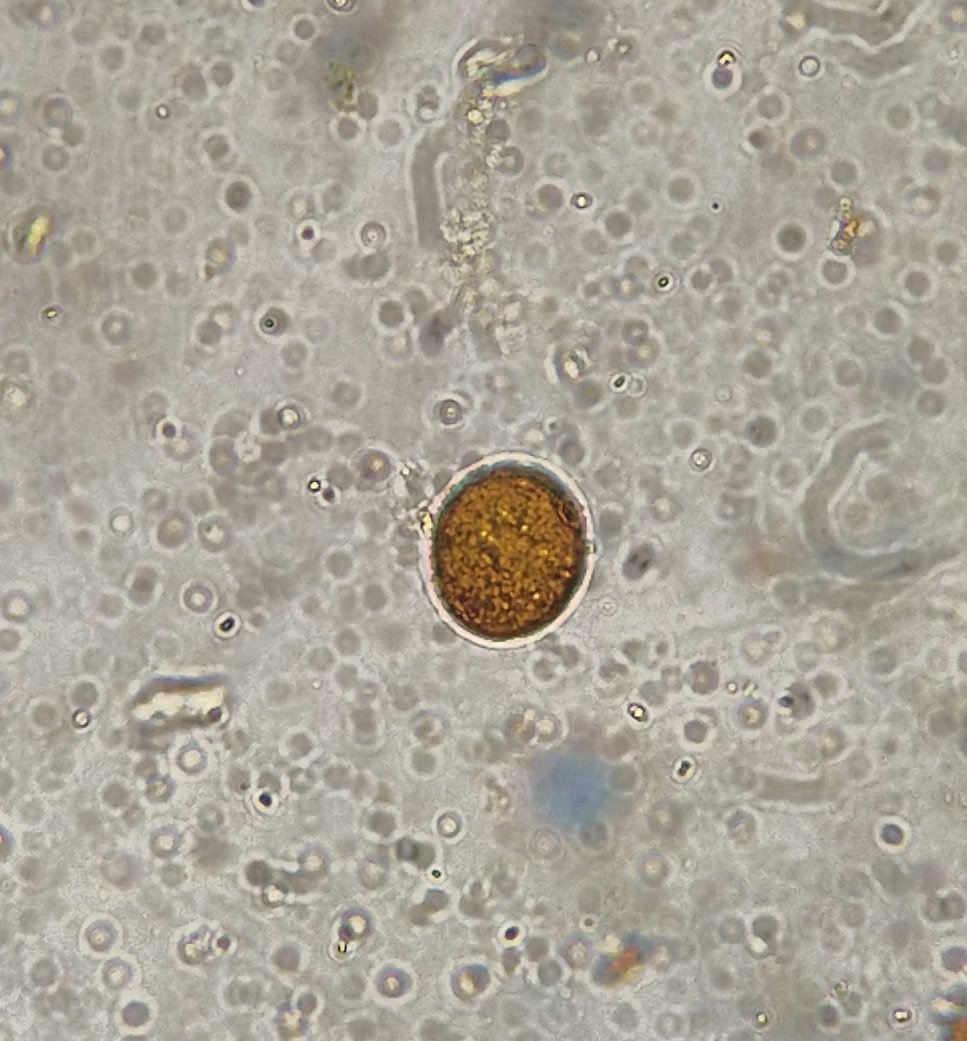

Здравствуйте. Помогите, пожалуйста, разобраться. Волнистый попугай, девочка, 3 года 5 месяцев. Лечили мегабактериоз, на вчерашней микроскопии ни одной мегабактерии, однако рвота и непереваренные зерна в помете остаются. Сделали рентген, орнитологи в замешательстве, у каждого свое отличное мнение по поводу преджелудка , печени и новообразовании в лёгких. В помете также нашли много пыльцы, однако возможно , что это глисты. Снова не понятно. Помогите , пожалуйста, разобраться с рентгеном и микроскопией. Фото прикладываю.